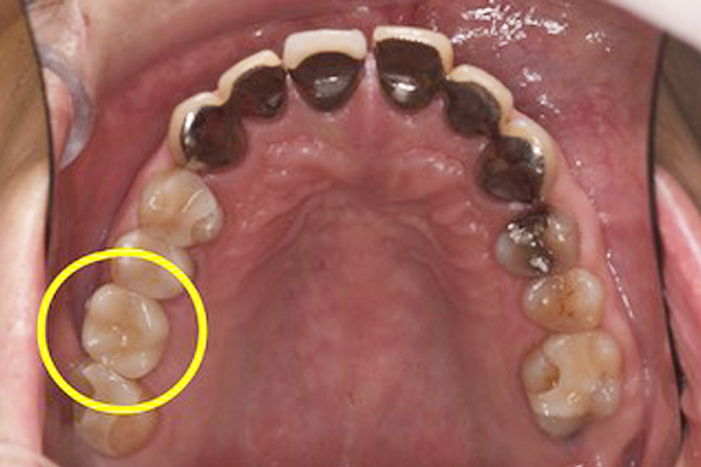

Before

After